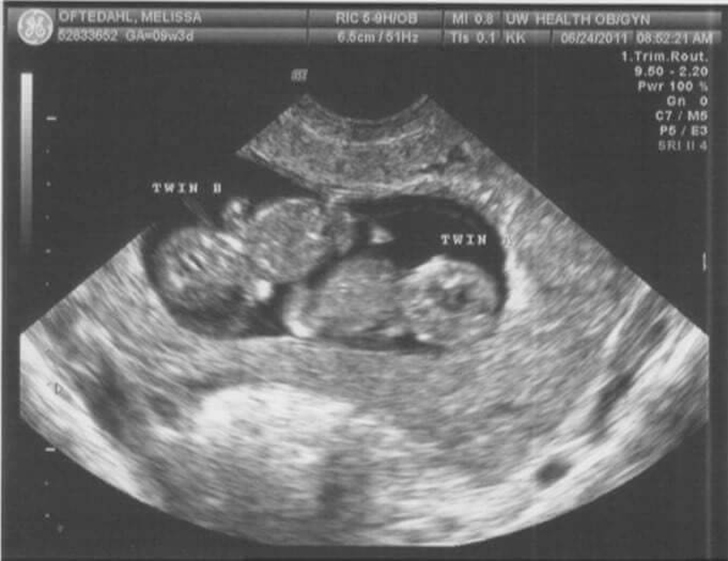

Would They Have Swiped Septuplets For Twins?